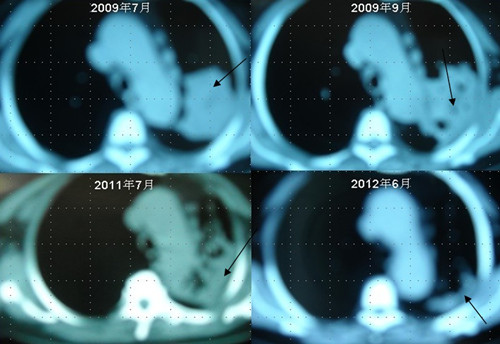

[提要] 患者李某某,女,64歲,于2009年6月因咳嗽、喘憋、痰中帶血,經CT及病理等相關檢查確診為右肺上葉粘液腺癌, 縱膈淋巴結轉移, 左胸膜轉移,胸腔積液,因病情及體質的原因無法接受手術及放化療等殺傷性治療,采用"中醫調胃、強腎、止血、化巖法"先后共治療8個月,現患者已有質量的存活近3年。目前隨訪患者飲食、睡眠、體力均好,可獨立完成日常家務,如今患者已經67歲。肺癌病人李XX的病理圖片肺癌病人李XX采用“董氏治癌法”治療前后CT變化

患者李某某,女,64歲,于2009年6月因咳嗽、喘憋、痰中帶血,經CT及病理等相關檢查確診為右肺上葉粘液腺癌, 縱膈淋巴結轉移, 左胸膜轉移,胸腔積液,因病情及體質的原因無法接受手術及放化療等殺傷性治療,采用"中醫調胃、強腎、止血、化巖法"先后共治療8個月,現患者已有質量的存活近3年。目前隨訪患者飲食、睡眠、體力均好,可獨立完成日常家務,如今患者已經67歲。

肺癌病人李XX采用“董氏治癌法”治療前后CT變化